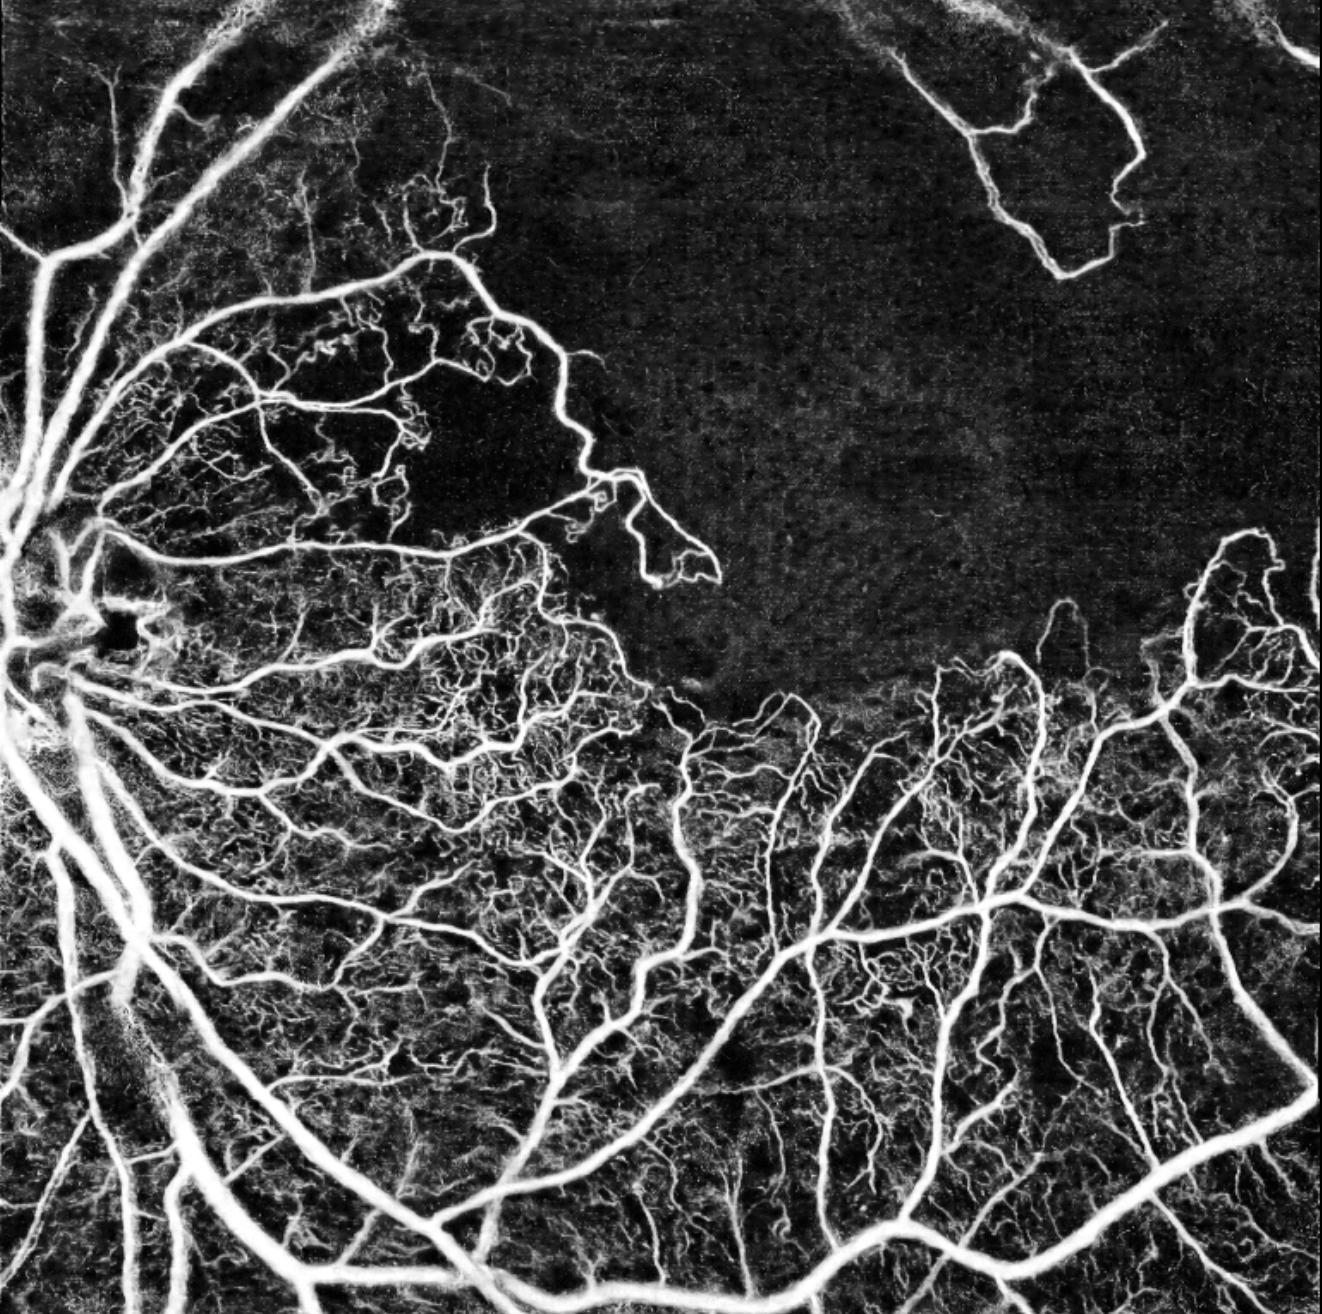

Angio-OCT montrant une occlusion capillaire étendue dans une rétinopathie diabétique

Angio-OCT Intalight — Occlusion capillaire dans une rétinopathie diabétique : zones de non-perfusion visibles en noir (IPO Paris)

Angiographie rétinienne

Injection intraveineuse de fluorescéine suivie de photographies séquentielles du fond d'œil. Elle révèle les fuites vasculaires, les zones d'ischémie rétinienne et les néovaisseaux. Indispensable pour guider les indications de laser et évaluer la sévérité de la rétinopathie.